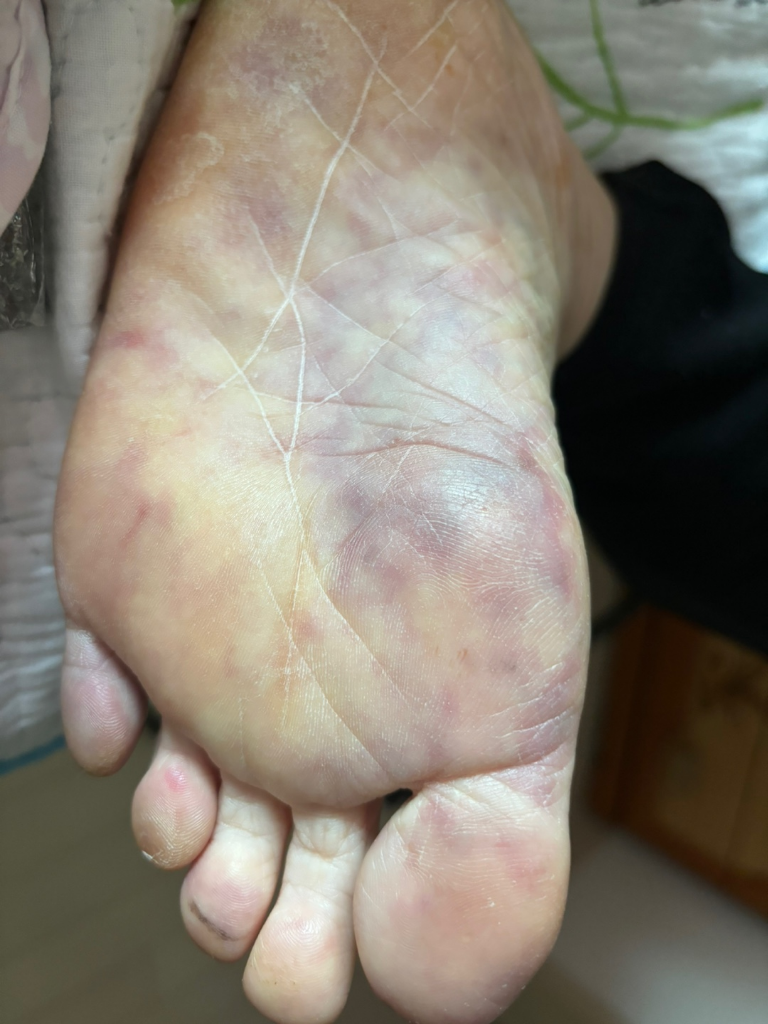

한 쪽 발바닥이 시퍼렇게 피멍이 들고

저리며 아주 차디차 많이 아파하시며

잠도 못 주무실 정도로 고통속에 소리를 지르시며

힘들어 하십니다 시술 받은 쪽 발 바닥이....

애끼 발가락은 까맣고 지금은 상태가 더 안좋아

지셔서 발바닥 전체가 까맣게 시퍼런 피엉이 전체를 덮어 파랐다 못해 까맣고 차디차 온기라곤 없이 변해있습니다.

시술 후 발이 시퍼렇게 변하고 차가우며 통증이 심한 것은 혈관손상이나 혈류 장애 가능성이 있어 매우 위험한 상태일 수 있습니다.

신장 시술과 직접적인 연관이 없다고 해도 시술 과정에서 혈액순환 문제가 발생했을 수 있으니 응급으로 혈관외과진료를 즉시 받아야 합니다.

피멍이 넓게 퍼지고 까맣게 변하는 것은 조직 괴사로 진행될 수 있어 지체하면 회복이 어렵습니다!